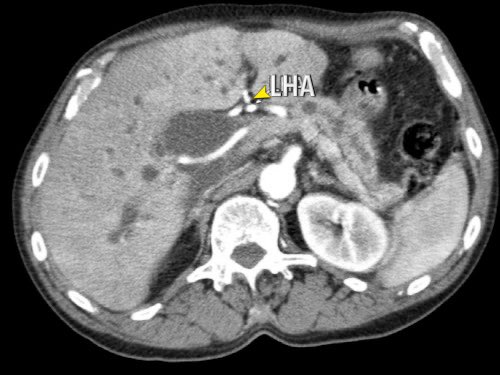

Các hình ảnh axial của cùng bệnh nhân có chú thích.

Hình MIP mặt phẳng đứng ngang này cho thấy một động mạch gan phải thay thế xuất phát từ phía phải của SMA (mũi tên vàng trong A).

Động mạch này đi qua vùng lân cận đầu tụy.

Hình CT axial cho thấy đường đi của động mạch gan phải thay thế phía sau tĩnh mạch cửa (đầu mũi tên vàng) và động mạch gan trái nguyên bản đi phía trước tĩnh mạch cửa (đầu mũi tên xanh lá).